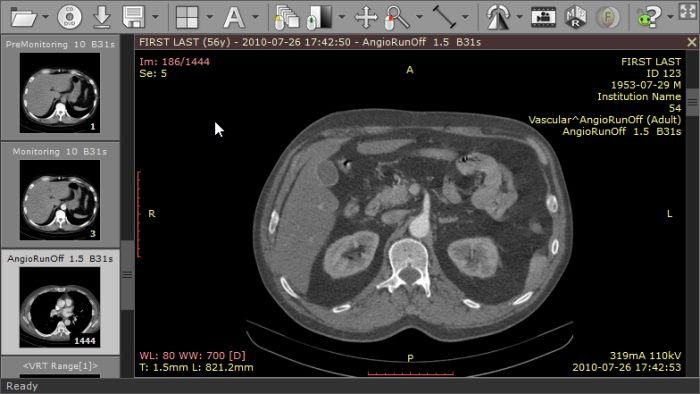

/DICOM (Digital Imaging and COmmunications in Medicine, цифровые изображения и обмен ими в медицине) - это индустриальный стандарт для передачи радиологических изображений и другой медицинской информации между компьютерами, опирающийся на стандарт Open System Interconnection (OSI), разработанный Международной организацией по стандартам (International Standards Organization, ISO). Стандарт DICOM описывает "паспортные" данные пациента, условия проведения исследования, положение пациента в момент получения изображения и т.п., для того чтобы в последствии было возможно провести медицинскую интерпретацию данного изображения.

Стандарт позволяет организовать цифровую связь между различным диагностическим и терапевтическим оборудованием, использующимся в системах различных производителей. Рабочие станции, Компьютерные (КТ) и Магнитно-резонансные Томографы (МРТ), микроскопы, УЗ-сканеры, общие архивы, хост-компьютеры и мэйнфреймы от разных производителей, расположенные в одном городе или нескольких городах, могут "общаться" друг с другом на основе DICOM с использованием открытых сетей по стандартным протоколам, например TCP/IP.

Стандарт DICOM версии 3.0 (окончательно выпущена в 1993 году) предназначен для передачи медицинских изображений, получаемых с помощью различных методов лучевой и иной диагностики, в его описании перечислено 29 диагностических методов. Данный стандарт получил широкое распространение в США, Японии, Германии и других странах.